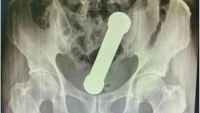

Um caso insólito ocorrido em um hospital de Manaus foi revelado na última quarta-feira (12) em uma renomada revista científica. De acordo com a publicação, um paciente deu entrada no centro médico com um peso de academia preso dentro do próprio corpo. A International Journal of Surgery Case Reports relatou que o paciente procurou o hospital sentindo fortes dores no estômago e relatando dificuldades para evacuar. Ele afirmou que sentia os sintomas há dois dias, mas não manifestou-se sobre uma possível causa do problema. O rapaz foi submetido a uma bateria de exames, incluindo um raio-X, que mostrou a presença do haltere de 2 kg. O objeto de cerca de 20 centímetros estava entre o reto e o intestino grosso do paciente. Após o causador do problema ser diagnosticado, o paciente admitiu que havia introduzido o objeto para prazer sexual. A equipe médica, então, sedou o homem e tentou a retirada do objeto com uma pinça. Como não obteve sucesso, foi obrigada a fazer a extração de forma cirúrgica. A operação transcorreu sem percalços, e o rapaz ficou três dias hospitalizado. Recuperado, ele recebeu alta e passa bem.